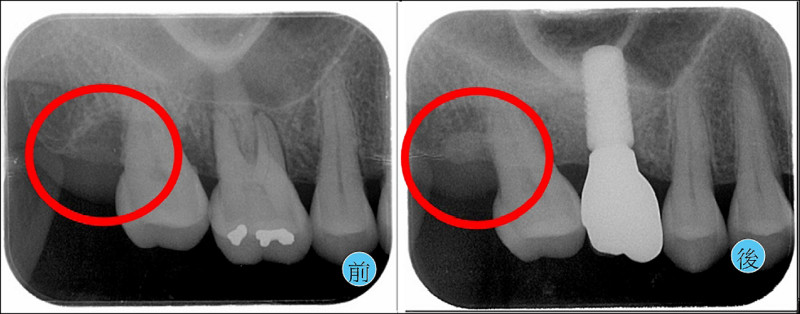

4.若條件允許,能在缺損處置入再生材料,期待將失去的骨質與牙根附著能再生(圖1)。

牙周囊袋深度已經降低至健康的2-3毫米,定期回診追蹤(圖2)。